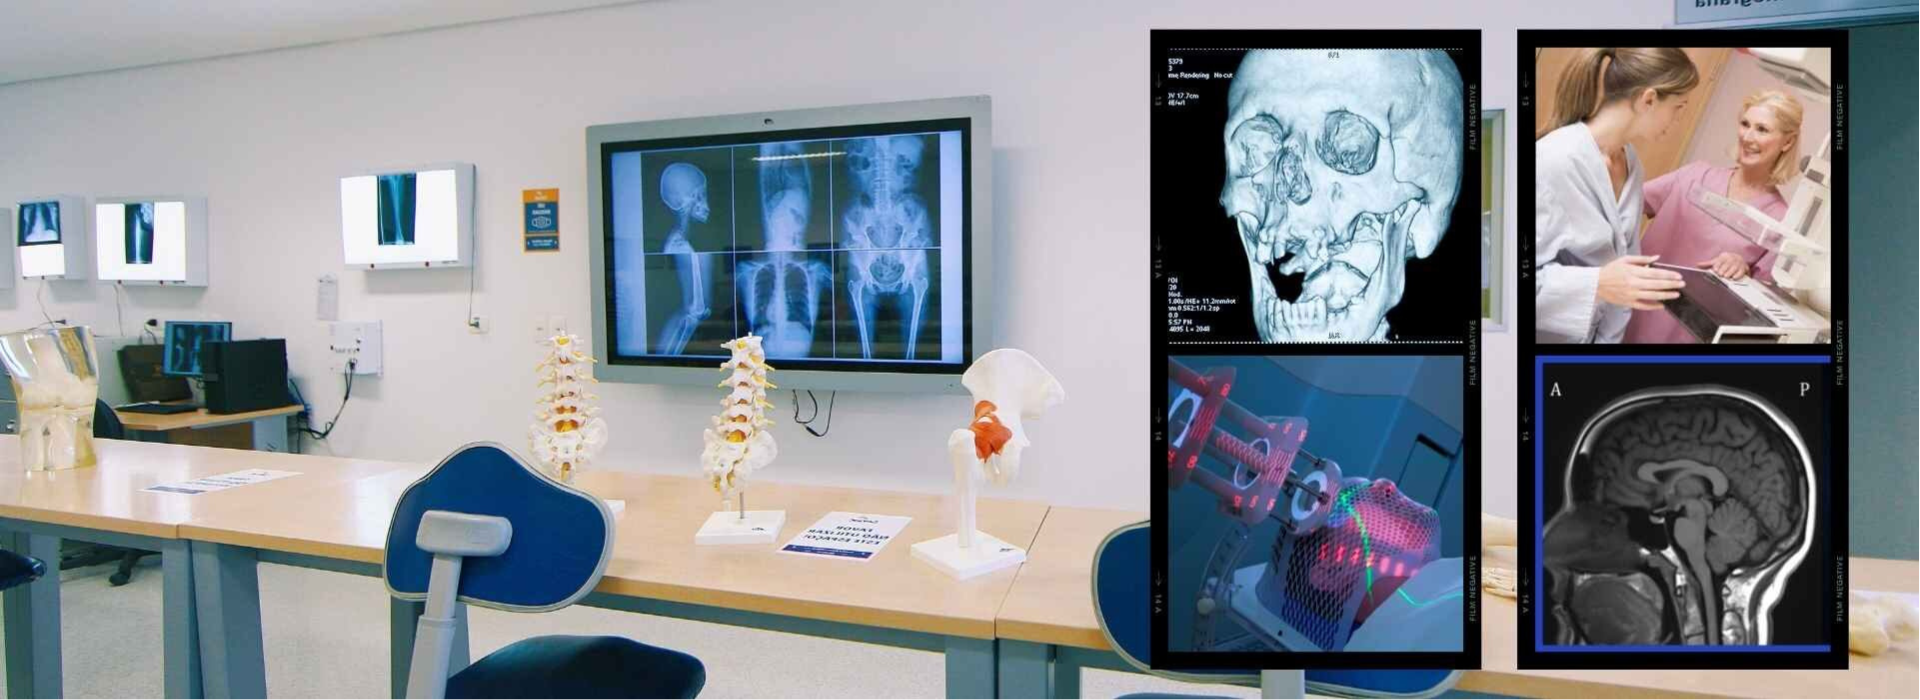

En el corazón de la comunidad, una visión de salud integral tomó forma. Fundada por un grupo de profesionales comprometidos con la prevención y el bienestar, nuestra empresa de diagnóstico por imágenes y rayos X se estableció con el propósito de proporcionar servicios de salud accesibles, precisos y de alta calidad.Desde nuestros inicios, hemos estado en constante evolución, adoptando tecnologia avanzada y metodologias innovadoras para ofrecer diagnósticos tempranos y efectivos.

En el Centro Médico Radiológico Virgen del Carmen ofrecemos el servicio profesional de Radiografías (Rayos X) con tecnología moderna y personal especializado, garantizando diagnósticos rápidos, precisos y confiables para el cuidado de tu salud. Nuestro centro radiológico está comprometido con brindar atención médica de calidad, seguridad y resultados oportunos, ayudando a detectar a tiempo diversas enfermedades y lesiones.